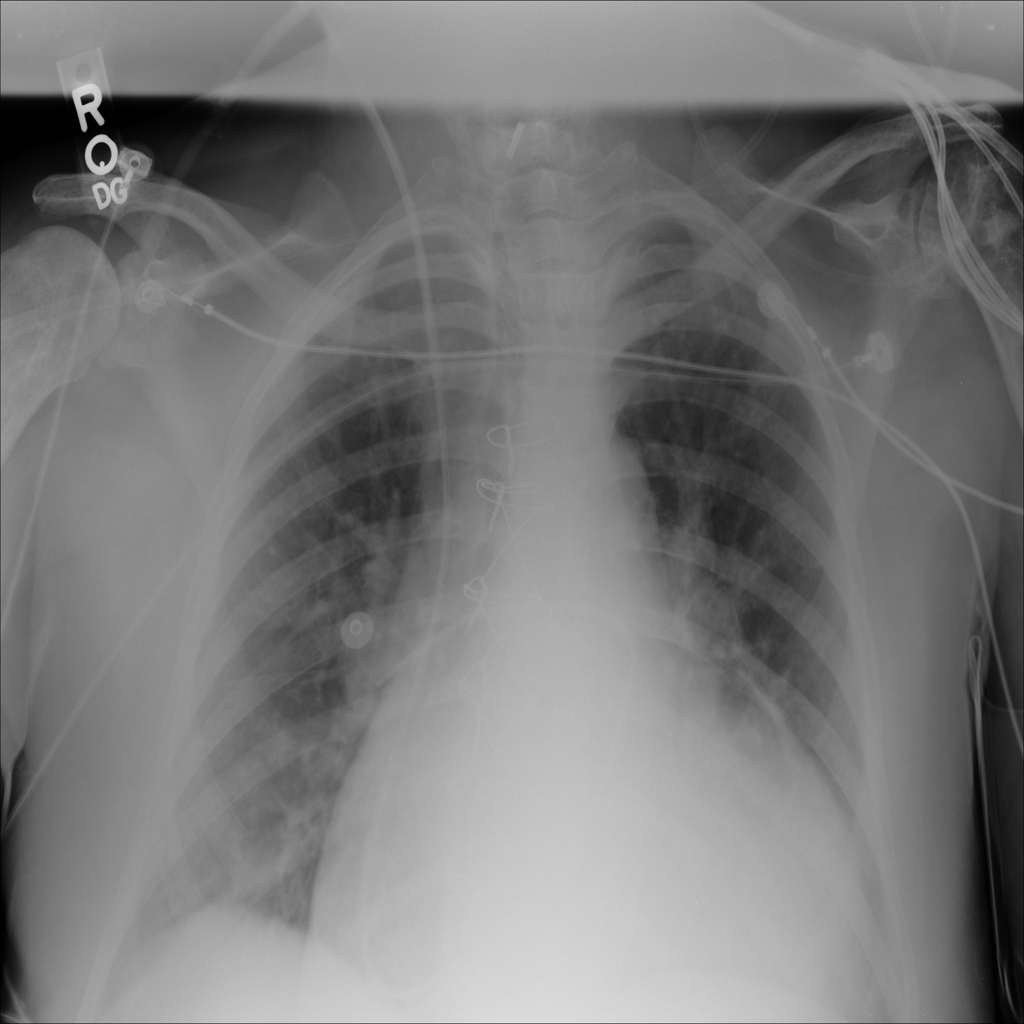

PAT-3384 · IMG-000Cardiomegaly

PAT-3384 · IMG-000

AP